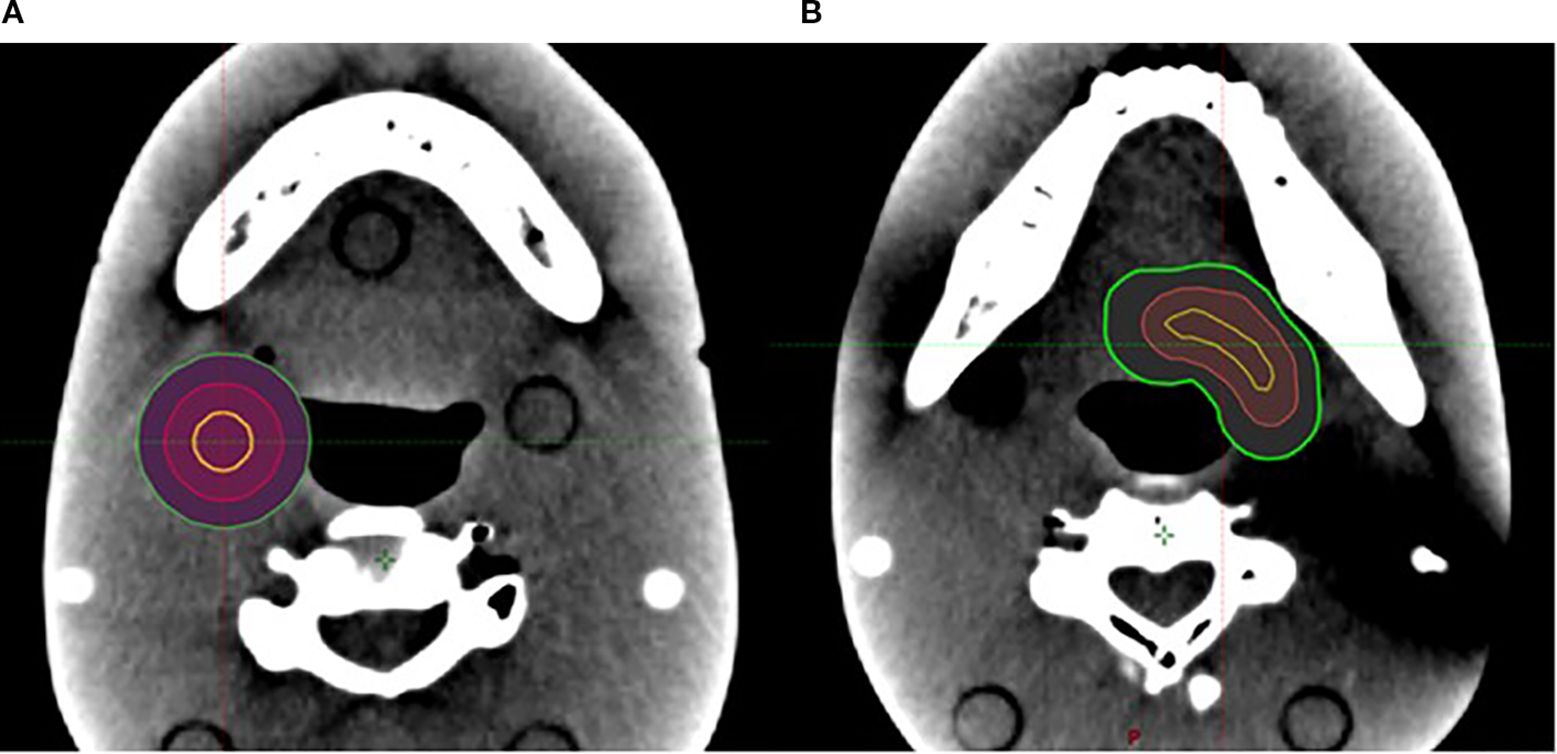

The VMAT plan used a 2-mm calculation resolution. For cases with one target, the SCART plan used two arcs, and the isocenter was placed at the center of the target. For cases with multiple targets, the isocenters of SCART plans that used a single isocenter were placed at the geometric center of all the targets, while the isocenters of dual-isocenter plans were placed at the center of each target (the dual-isocenter technique was used for cases of two targets only). For the irregularly shaped targets, a conformal V_SHDCx (i.e., V_cSHDCx) contour with its margin subtracted from the irregularly shaped target was also used for planning. The volume of V_cSHDCx was equivalent to the volume of spherical V_SHDCx of 1-cm diameter (Figure 3). Dosimetric comparisons were performed for plans using V_cSHDCx and V_SHDCx. Table 1 demonstrates the detailed dose constraints used for SCART optimization.

Figure 3. (A) One 1-cm-diameter spherical V_SHDCx (yellow) was placed in the middle of a spherical target. (B) One V_cSHDCx in yellow was placed in the irregularly shaped target (volume equivalent to the spherical V_SHDCx of 1-cm diameter). Red, GTVx_central; green, GTVx.